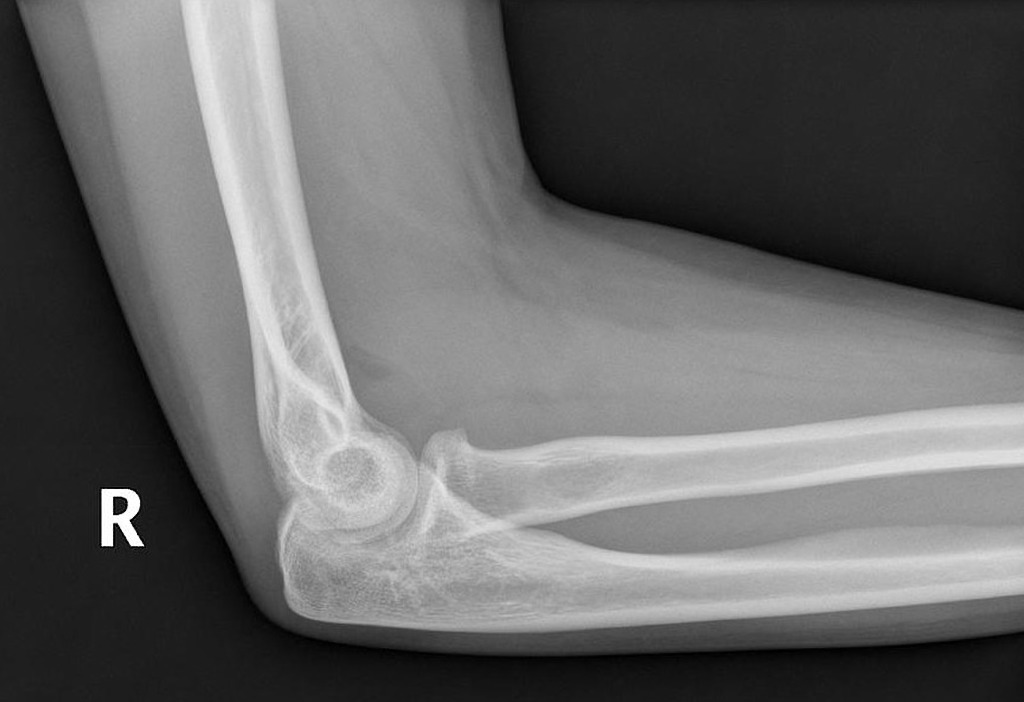

Xray of patient with gout. Is this an elbow joint effusion? How can you tell?